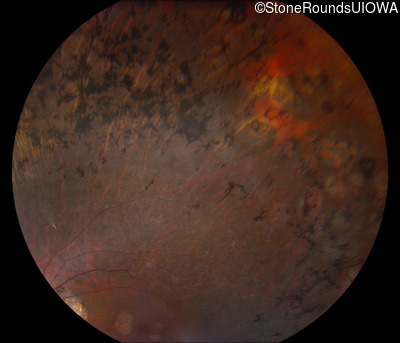

Fundus Photography - Right - 20/25 -2 sc

Exemplar

Fundus Photography - Left - 20/25 sc